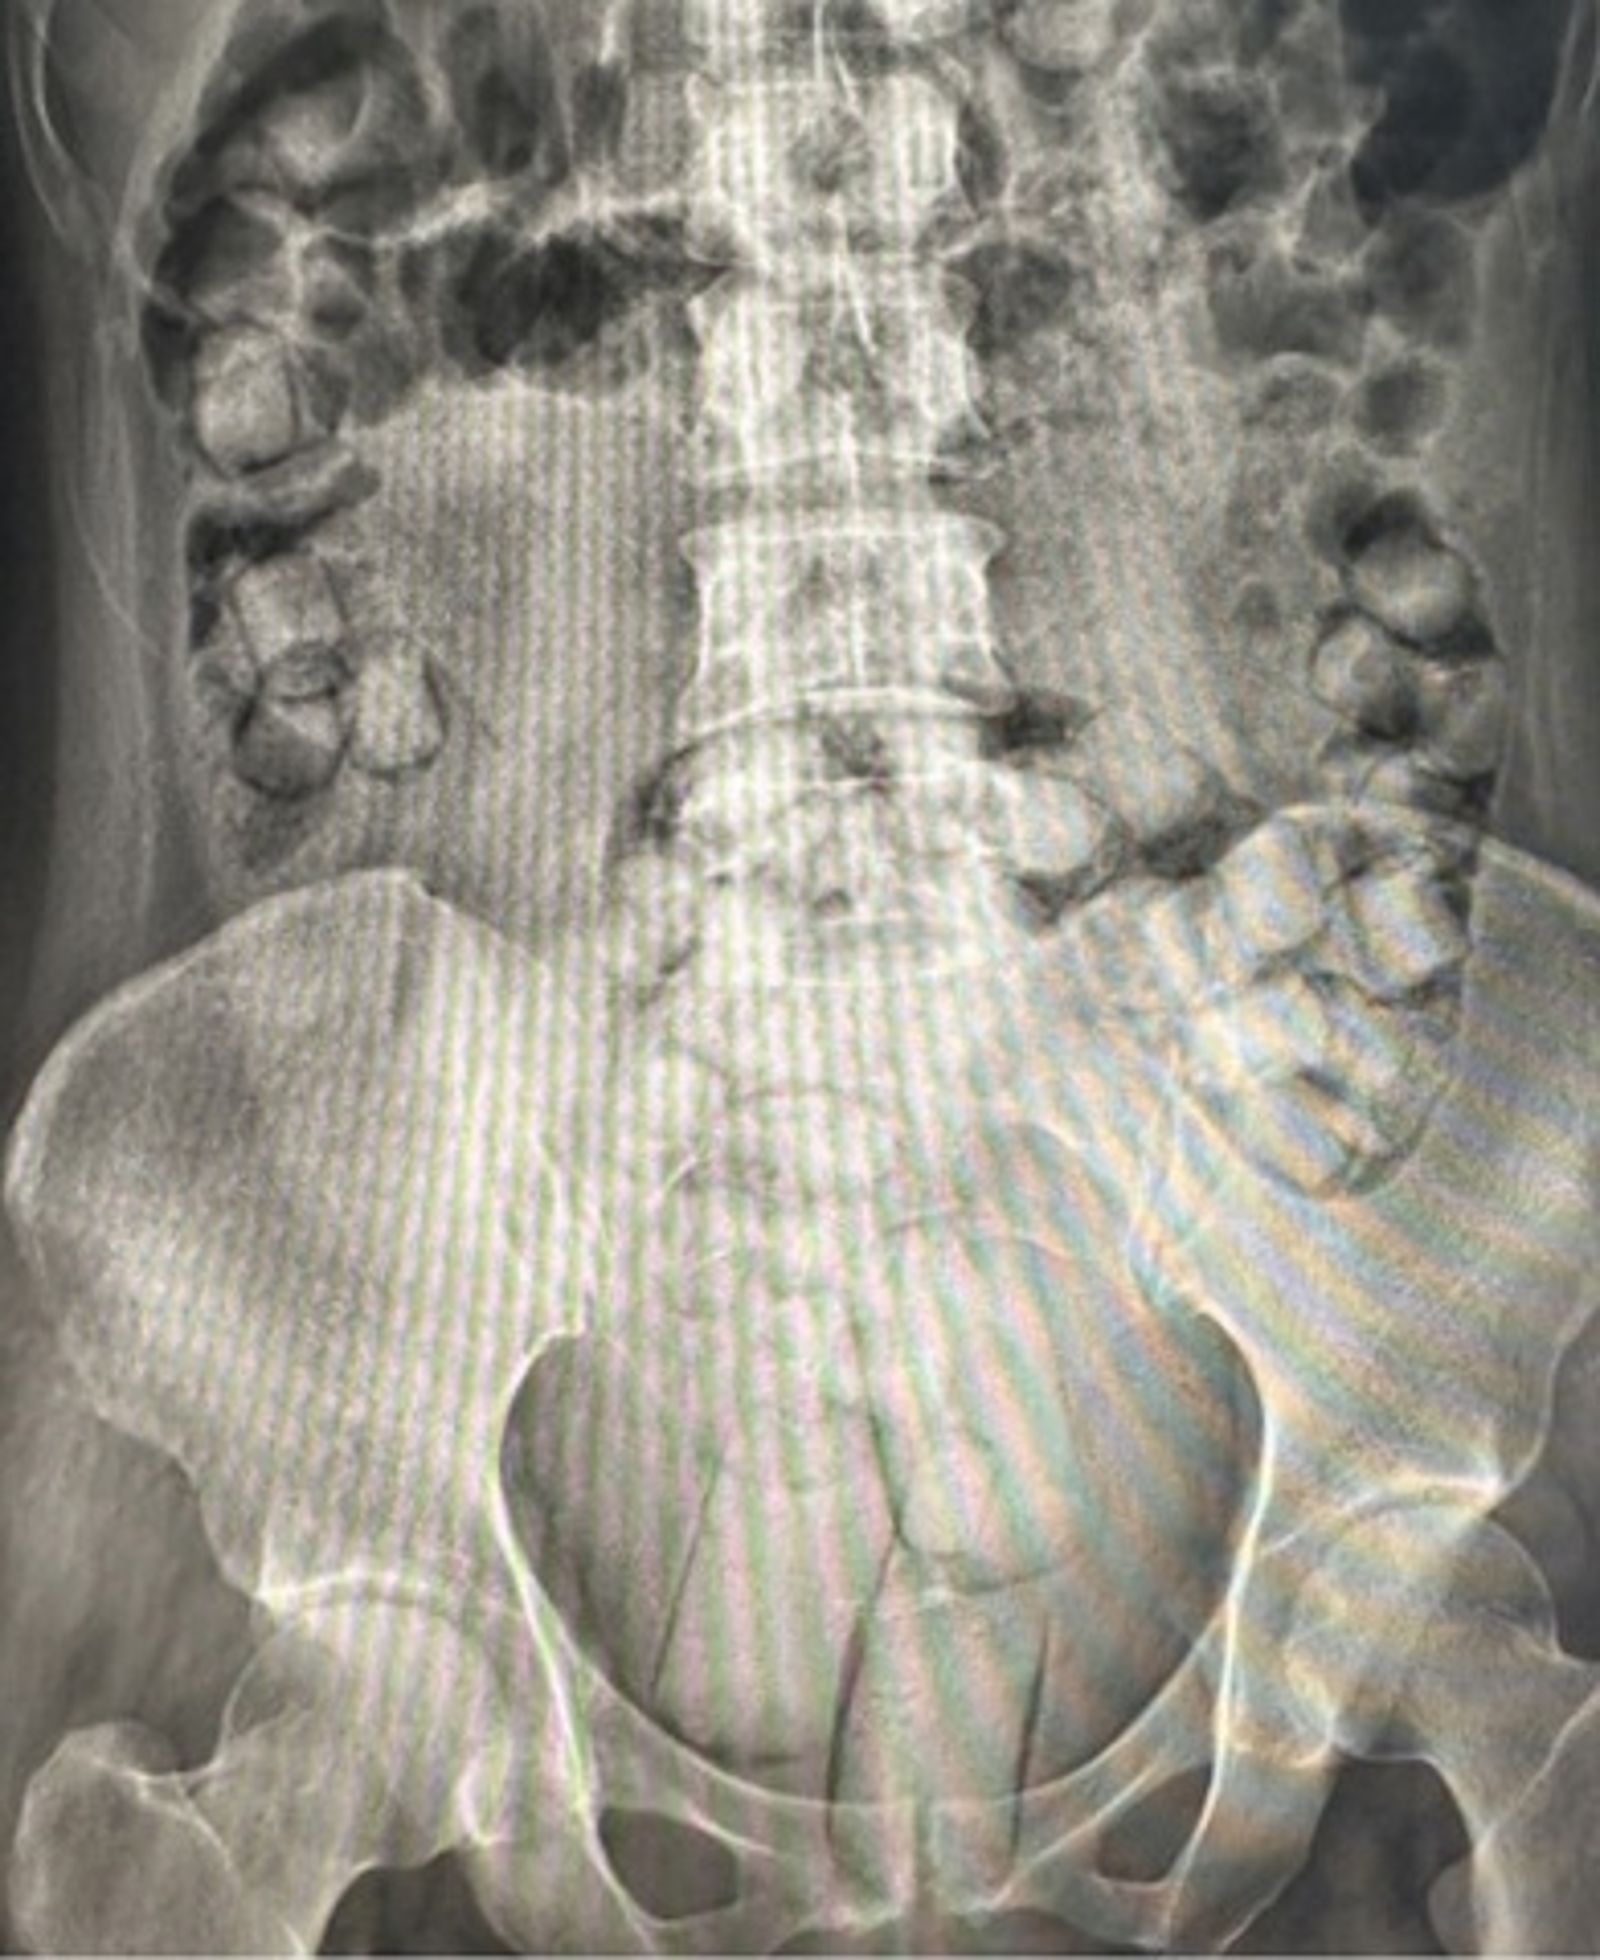

去年10月12日,專案小組掌握毒品人口葉男、蘇女及羅女即將回國的確切航班,出動14名警力在桃園國際機場第一航廈嚴陣以待。3人入境隨即被攔獲並送醫檢查,醫護人員分別從3人的肛門與陰道內,起出總重588.54公克的海洛因,當場讓辦案人員看傻了眼。